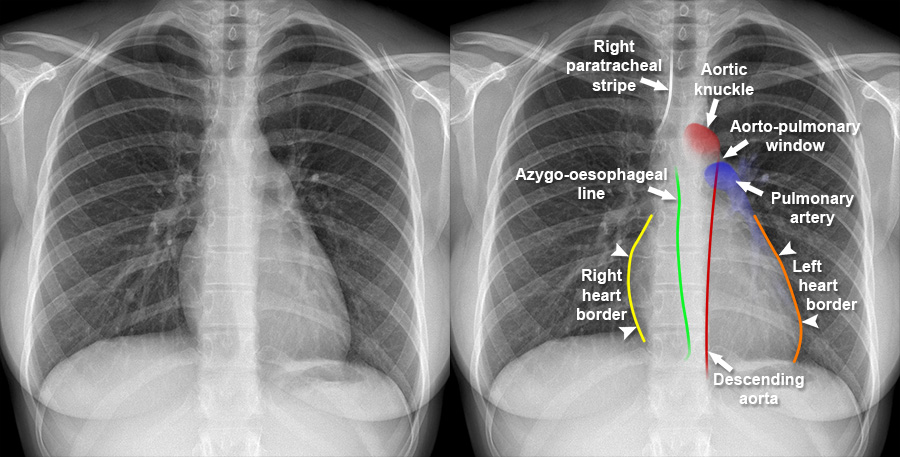

Chest X Ray Mediastinum Images

Hilum Chest X Ray Vrogue co

Hilum Chest X Ray Vrogue co

Aortic Dissection X Ray Wikidoc

Widened Mediastinum In A Child With Severe Trauma CMAJ

Retropharyngeal Space X Ray